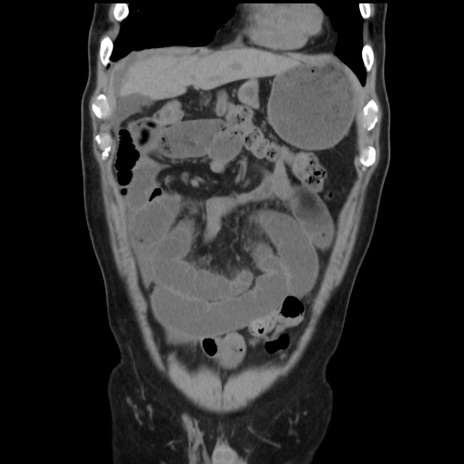

症例16(冠状断像)

【症例】 70歳代男性

【主訴】 腹痛、嘔吐

【現病歴】 約1ヶ月前より間欠的に腹痛と嘔吐あり、当院消化器内科を受診したところCTで多発する肝臓のLDAを指摘され、精査中であった。以降は消化器症状は安定していたが、2日前より嘔気と腹痛があり、同日より排便・排ガスが消失した。改善認めず、 本日、救急外来を受診した。

【身体所見】意識清明・会話良好、BT 36.3℃、BP 127/80mmHg、 P 80bpm、腹部:膨満あり、平坦・軟、上腹部正中および下腹部正中に圧痛あり、反跳痛なし、筋性防御なし。

【データ】WBC 7200、CRP 0.77